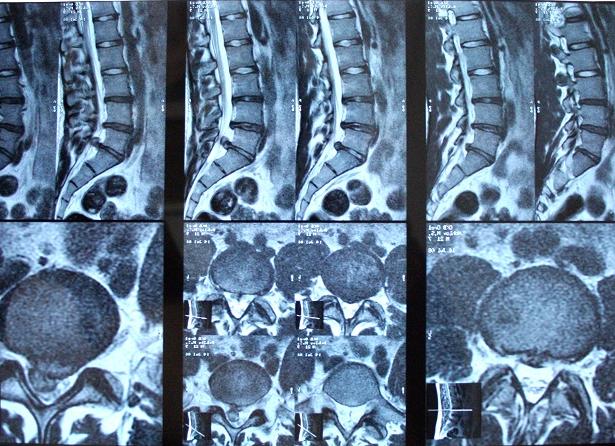

Стрелками на МРТ-снимке указаны межпозвоночные грыжи

При МРТ поясницы снимки делаются в двух плоскостях проекций: сагиттальной и поперечной. Возможно использование контраста для уточнения границ новообразований, отдельных элементов, недостатка информативности снимков.

Аппарат во время исследования делает компьютерные послойные снимки, на которых в различных ракурсах отображается состояние позвоночника и близлежащих тканей.

Результат представляет собой серию послойных изображений исследуемой области, выполненных в двух проекциях. Расшифровка сделанных снимков происходит по окончании процедуры в течение нескольких минут.

При обследовании поясничного отдела делают три проекции: две из них параллельно спинному мозгу и каждый межпозвонковый диск.

Цель именно такой техники обследования – наличие изображений, несущих информацию, которые отображают поясничный отдел от правого до левого поперечного отростка.

Точный анализ выполняется в двух проекциях – сагиттальной и поперечной. Исследование проводят на уровне поражения косной ткани с оптимальной толщиной виртуальных срезов от 3 до 4 мм, без зазоров. Сканируя поврежденные места, врач легко подбирает методы восстановления позвоночника.